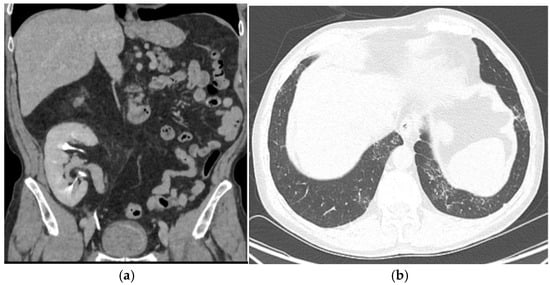

2. Case Presentation